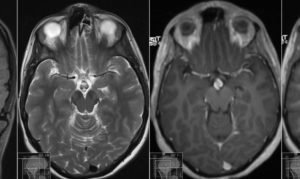

МРТ гипофиза проводится с контрастом (гадолинием) и без него. Процедура позволяет получить четкое и подробное изображение всех трех долей железы и ее сосудов. Помимо этого, происходит визуализация зрительного перекреста (хиазмы) и всего головного мозга.

При расшифровке специалист обращает внимание на размеры железы, ее расположение, структуру и однородность ткани, ее кровоснабжение, при наличии новообразования – степень инвазивности в окружающие ткани.

Что касается самого гипофиза, то для диагностики его опухоли обязателен контраст, позволяющий визуализировать образование размером более 3-4 мм.

Сами новообразования во время томографии позволяют выявить так называемый “эффект массы” – смещение и деформацию рядом расположенных структур патологической тканью.

Клинически это проявляется проблемами со зрением и повышением внутричерепного давления. Само новообразование выявляется как повышенный сигнал на томограмме.